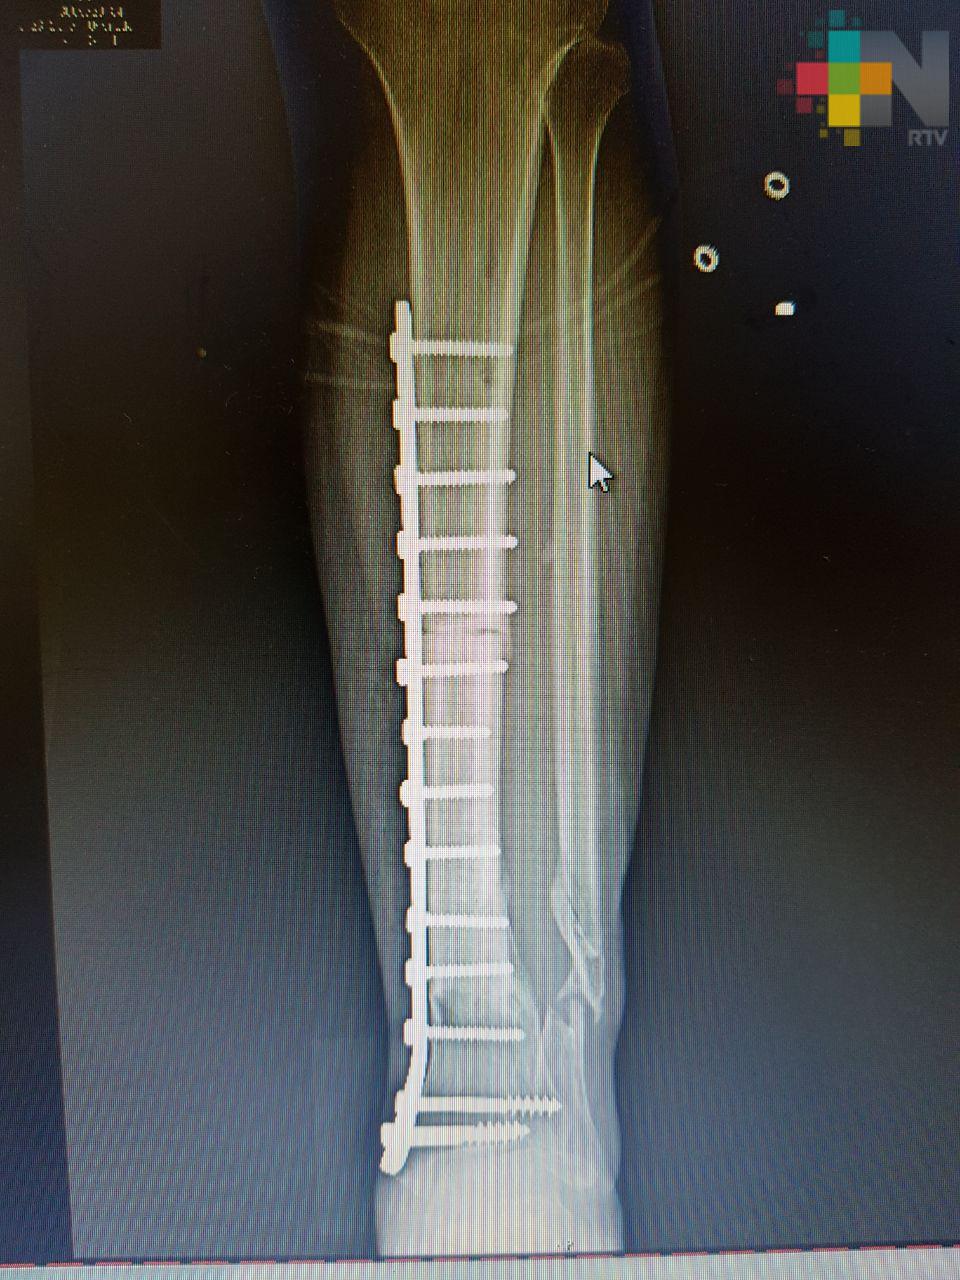

Xalapa, Ver.- Un equipo médico multidisciplinario del Instituto Mexicano del Seguro Social (IMSS) en Veracruz restituyó 11 centímetros de hueso de la pierna de un hombre que sufrió un accidente, mediante el trasplante de tejido óseo cadavérico que le permitió conservar la extremidad y volver a caminar.

El hueso implantado se obtuvo del Banco de Tejidos en el Estado de México a solicitud expresa de los médicos tratantes. El injerto fue realizado en el Hospital General de Zona No. 11 «Ignacio García Téllez», de la ciudad de Xalapa.

Fue aproximadamente una pérdida de 11 centímetros de hueso, por lo que al llegar al hospital se le realizaron cirugías para preservar la viabilidad de los tejidos afectados y la colocación de placas en las partes óseas.

Sin embargo, se buscó la forma de salvar el miembro y mediante la recuperación de la viabilidad de los tejidos blandos se optó por el implante óseo. El doctor Morales explicó que en este caso se activó el protocolo para solicitar tejido óseo y al cabo de algunos meses se logró obtener el hueso de un cadáver apto para implantarse.

Fue necesario recurrir a un implante de hueso porque era una lesión muy extensa. No había sustento, no había hueso, no había de dónde fijar la placa. Era prácticamente una pérdida total, el pie estaba suelto y no había soporte que uniera esas dos estructuras, explicó el especialista. El riesgo de pérdida de la extremidad fue alto y el proceso de recuperación fue de aproximadamente un año.

La recuperación del hueso está al 100, ya tiene una integración radiográfica del injerto y debe continuar con el ejercicio de deambulación, puntualizó.